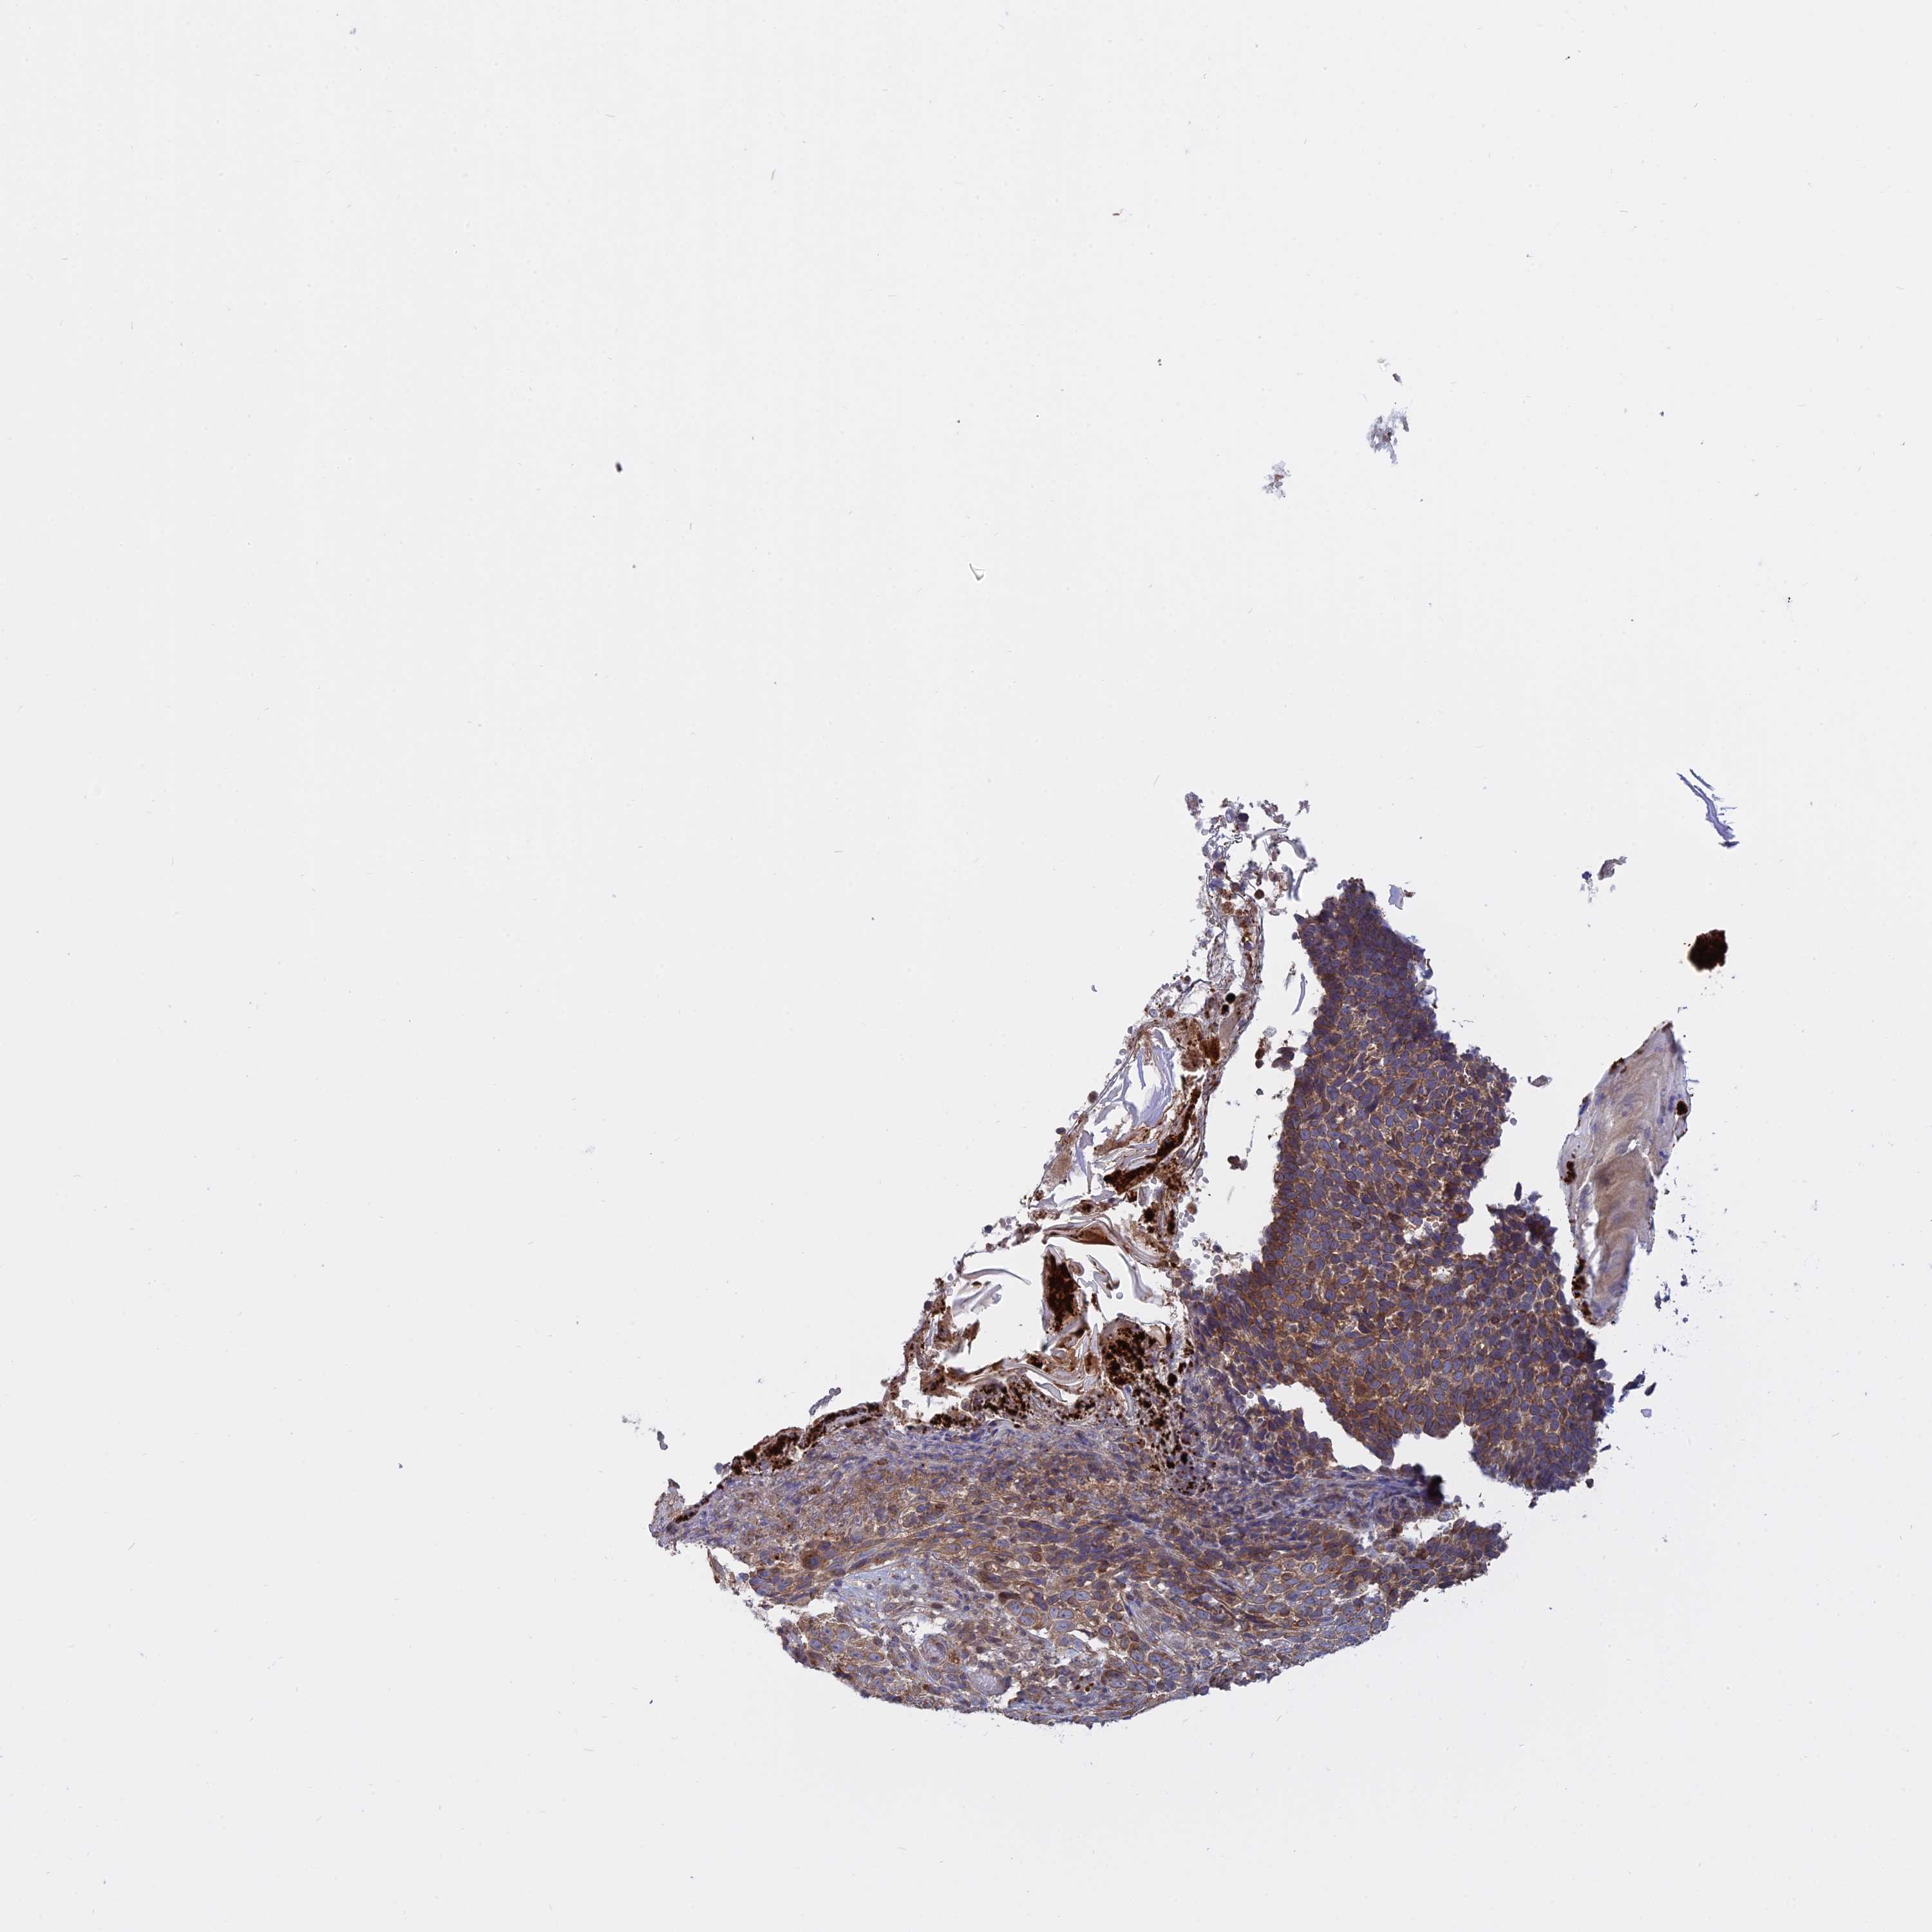

SKIN CANCER - Protein expressioni

A mouse-over function shows sample information and annotation data. Click on an image to view it in a full screen mode. Samples can be filtered based on level of antibody staining by selecting one or several of the following categories: high, medium, low and not detected. The assay and annotation is described here.

Antibody stainingi

Antibody staining in the annotated cell types in the current human tissue is reported as not detected, low, medium, or high, based on conventional immunohistochemistry profiling in selected tissues. This score is based on the combination of the staining intensity and fraction of stained cells.

Each image is clickable and will lead to virtual microscopy that enables deeper exploration of all samples and also displays staining intensity scores, fraction scores and subcellular localization as well as patient and tissue information for each sample.

Antibody HPA042296

Staining

High

Medium

Low

Not detected

Intensity

Strong

Moderate

Weak

Negative

Quantity

>75%

75%-25%

<25%

None

Location

Nuclear

Cytoplasmic/membranous

Cytoplasmic/membranous,nuclear

Basal cell carcinoma

Squamous cell carcinoma, NOS

Squamous cell carcinoma, metastatic, NOS